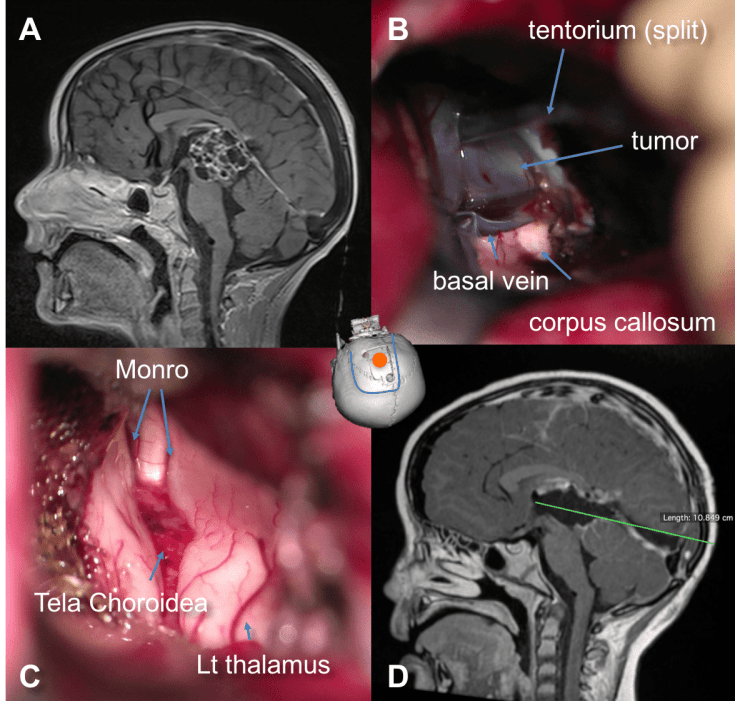

la voie inter-thalamo-trigonale

2 variantes :

- voie sous-choroïdienne : en soulevant la toile choroïdienne

- voie trans-choroïdienne : en décollant le trigone de la toile choroïdienne, ou même en réséquant ce dernier

elle donne accès à la partie moyenne et postérieure du V3, à la région de l’aqueduc, à la

partie haute du mésencéphale,et aux tumeurs naissant à la face interne ou postéro-supérieure du thalamus.

elle est limitée en arrière par la lyre du trigone

elle permet d’aborder des tumeurs de la pinéale à développement antérieur

l’accès à la partie postérieure du V3 nécessite un abord transcalleux un plus antérieur, de façon à être ensuite parallèle au corps du corps calleux (Cf. ci-contre).